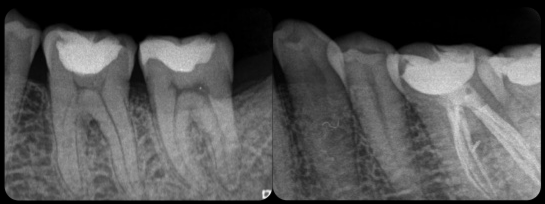

- CASE1.珍しい6本の神経管の抜髄根管治療

- 奥歯の神経管の数は3~4本とされていますが、今回の歯の神経管は6本の複雑な形態でした。顕微鏡下で丁寧な治療を行うことでより予知性の高い治療が可能となります。